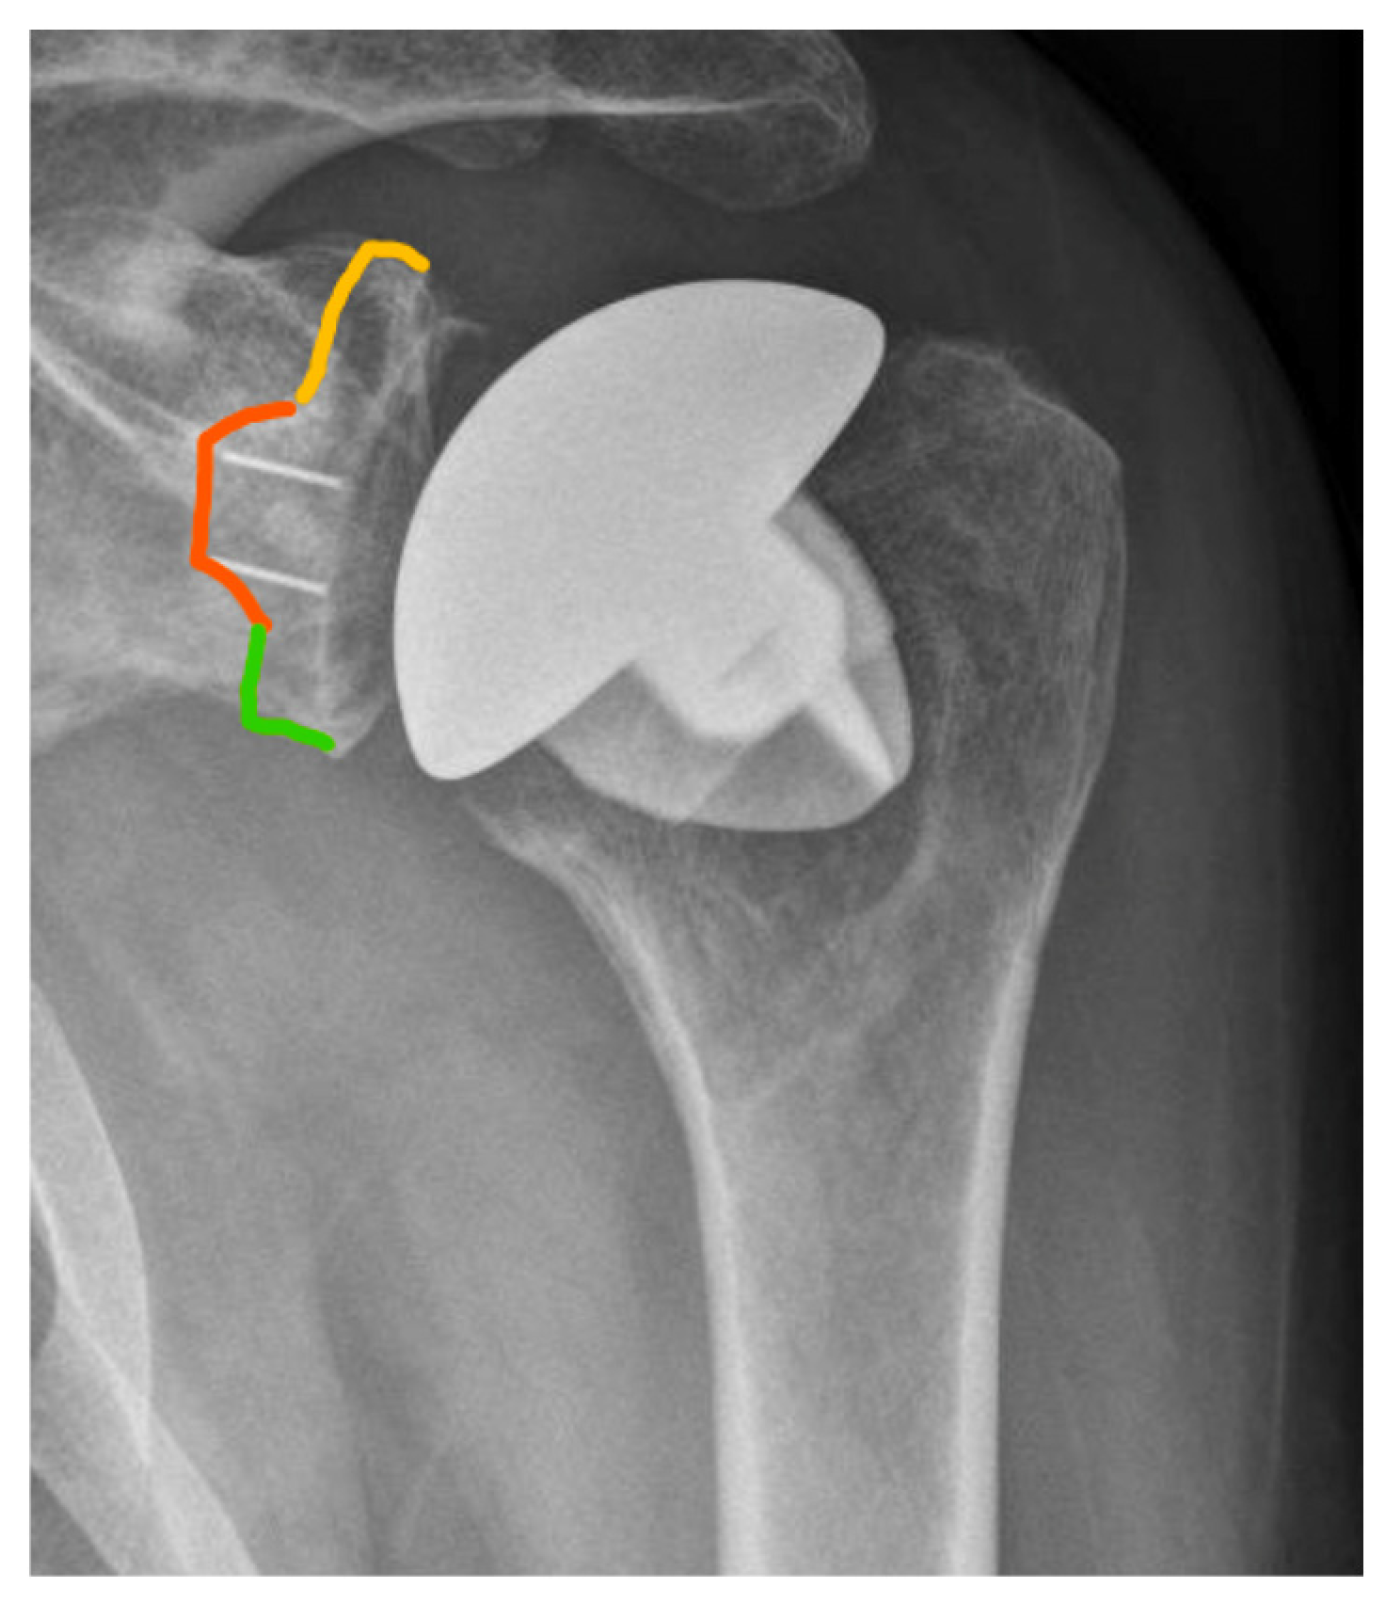

2.2. Radiographic and Clinical Evauation

2.4. Radiographic Assessment